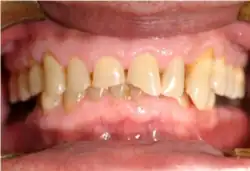

- parfois de troubles de la sphère ORL[8], et notamment asthme[9],[10],[11],[12],[13],[14], laryngite[15],[16], toux[17] ou érosion dentaire[18],[19],[20] ;

La maladie a été redéfinie lors d'une conférence de consensus (2006) qui a porté sur 50 points[1] comme une affection qui se développe lorsque le reflux du contenu de l'estomac provoque des symptômes et/ou des complications gênantes. Elle a été sous-classée en syndromes œsophagiens et extraœsophagiens. Et cette nouvelle définition a inclus une approche centrée sur le patient (indépendante des résultats endoscopiques), une sous-classification de la maladie en syndromes discrets ; de plus la laryngite, la toux, l'asthme et des érosions dentaires sont ajoutés comme signes syndromiques possibles[1].

- manifestations ORL : enrouement[45] ; manifestations stomatologiques : carie dentaire, gingivite ;